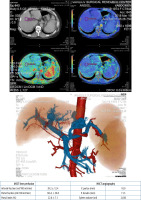

As demonstrated in Figures 5 and 6, the sample indicators of liver perfusion are shown in both health and LC states. It is also important to note that MSCT examinations allow for the identification of the particular features of the portal system angioarchitecture. This is important in the planning of surgical options, including palliative surgeries such as portosystemic shunting or disconnecting interventions, as well as definitive treatment, i.e. liver transplantation. The visualisation of vasculature facilitates the identification of distinctive features in the architecture of the portal and arterial systems.